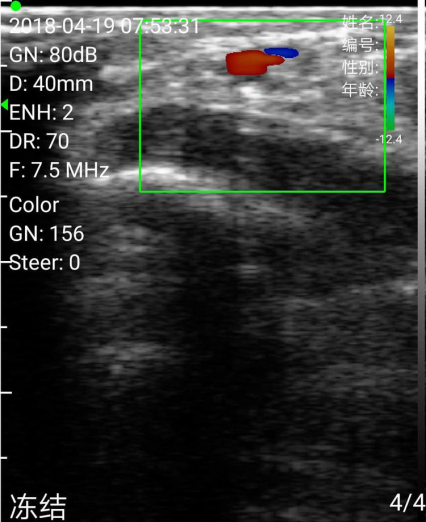

横切确定尺动脉

测量尺动脉流速(这个功能很给力)